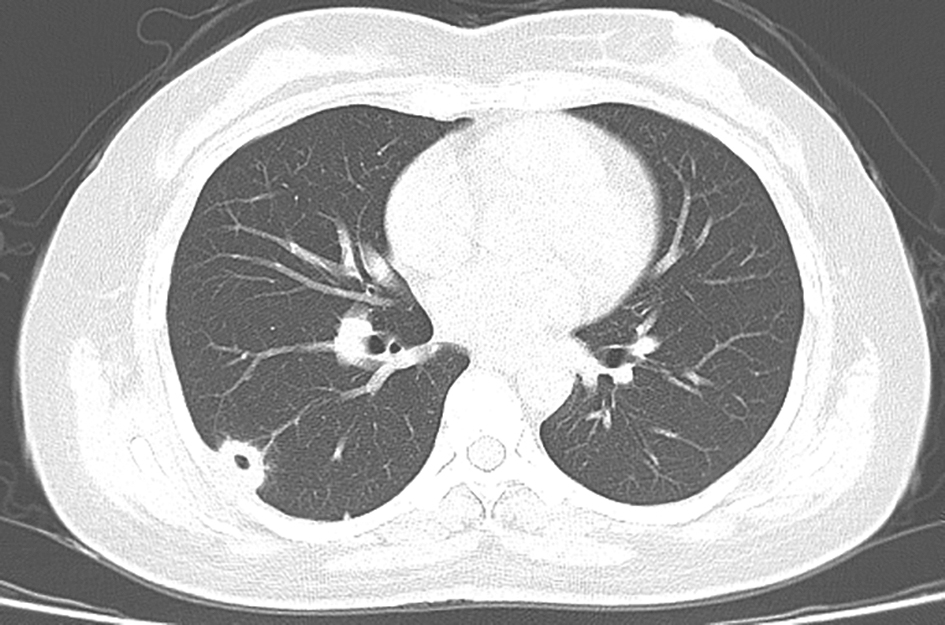

图3 金黄色葡萄球菌败血症所致肺脓肿胸部CT表现

图4 肺结核空洞胸部CT表现

胸部CT见周围卫星灶及树芽征

可为吸入性肺脓肿、血源性肺脓肿及继发性肺脓肿。吸入性肺脓肿多为单发,伴有咳脓臭痰、高热。血源性肺脓肿多由细菌血行播散所致,常见于金黄色葡萄球菌败血症,可表现为多发小的薄壁空洞,即液气囊腔(图3),可进展迅速,常伴有发热。继发性肺脓肿可为肺炎后肺脓肿、阿米巴性肺脓肿等,多为单发空洞。

肺结核空洞常为厚壁空洞,周围可有肉芽肿性肺实变、纤维化或钙化区,可伴有卫星灶或树芽征(图4)。患者可有乏力、低热、盗汗等结核中毒症状,或临床症状不典型。